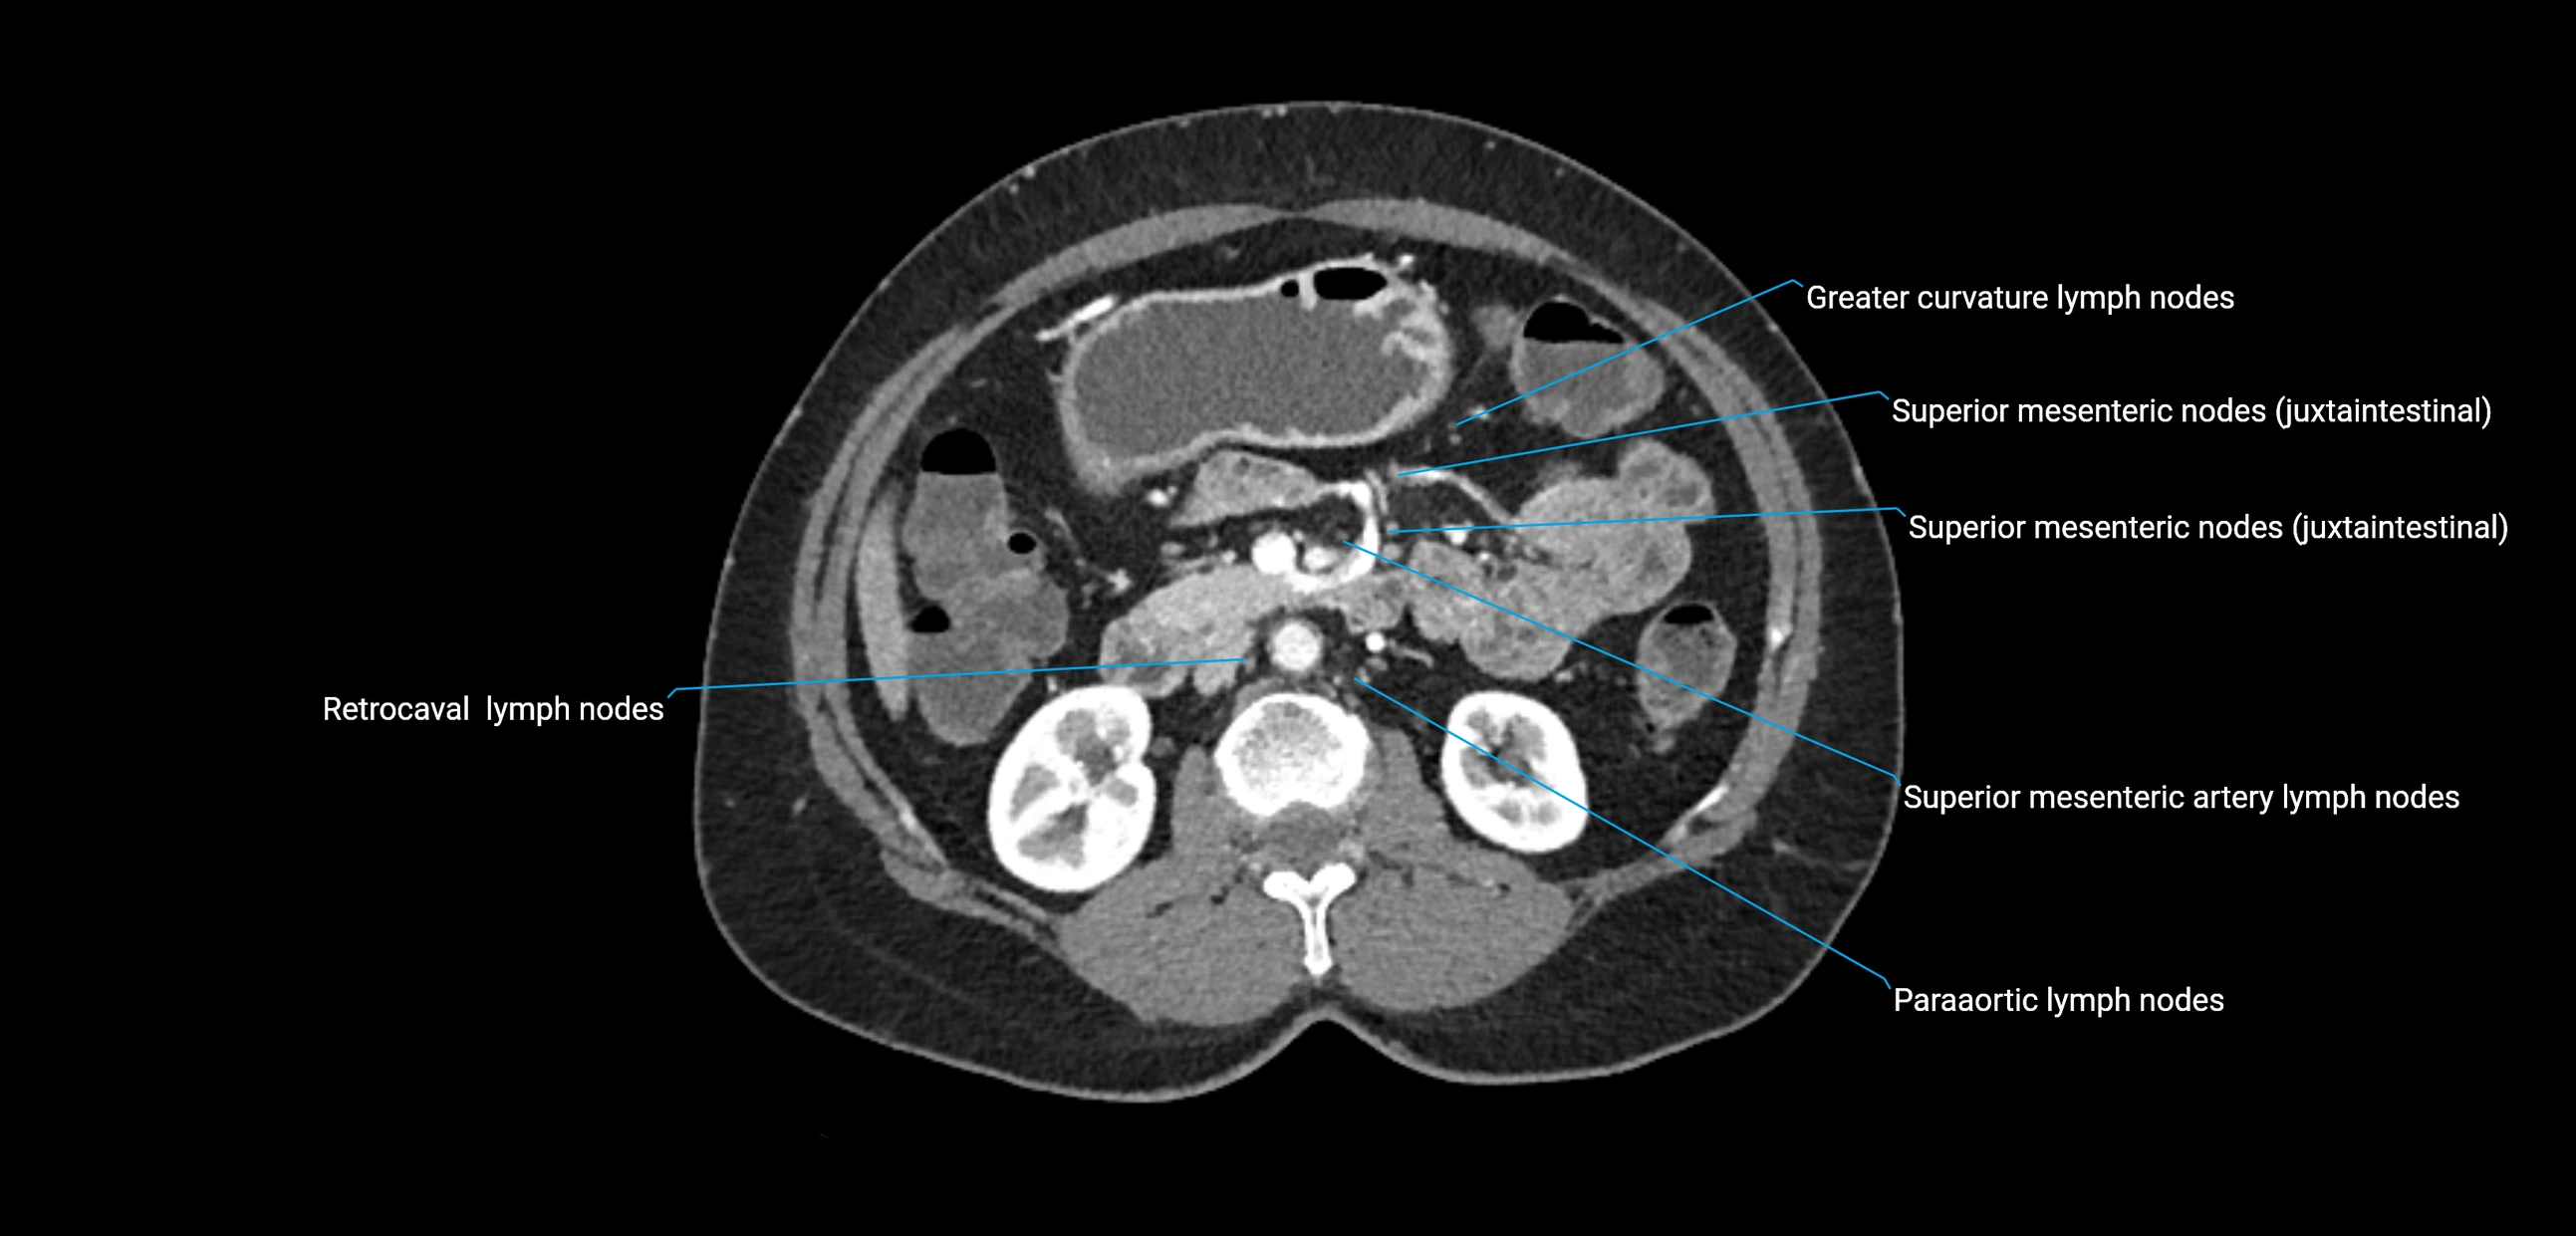

MRI images

image